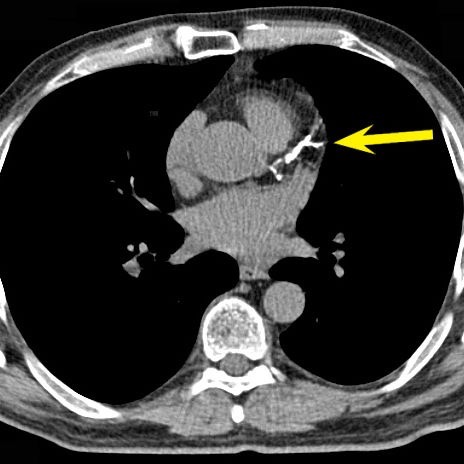

Gambar 2. Gambaran tumpukan plak berkalsifkasi pada pembuluh darah koroner yang terlihat pada CT scan.